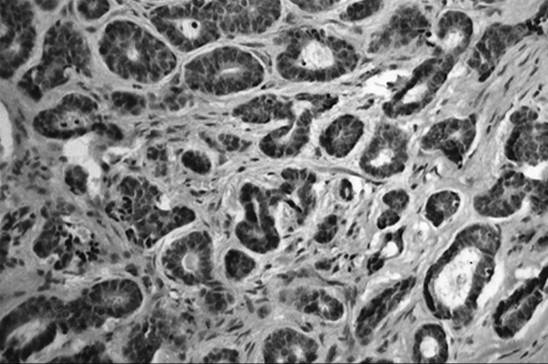

Patients with VIN most commonly present with pruritis and vulvar lesions. These lesions may appear scaly, white, red, or hyperpigmented (Fig. 51.1, Fig. 51.2, Fig. 51.3 and Fig. 51.4). Careful inspection with 5% acetic acid and liberal use of punch biopsy are the cornerstones of diagnosis. An underlying malignancy may be present in 7% to 22% of patients who undergo surgical excision for vulvar carcinoma in situ. Wide local excision with at least a 5-mm margin is the preferred management option as it allows pathologic confirmation and is associated with less morbidity than skinning vulvectomy. Skinning vulvectomy with split thickness skin graft may be an option in patients with widespread disease. Laser ablation is also an effective nonmutilating option in patients with multifocal or clitoral disease. Recurrences are frequent (10%–50%) despite negative surgical margins and therapy should be tailored to symptom control and ruling out underlying malignancy. Patients should be followed every few months with careful visual inspection of the vulva and taught self-exam skills as well.

FIG. 51.4. Vulvar carcinoma in situ with full thickness involvement of dysplastic cells.